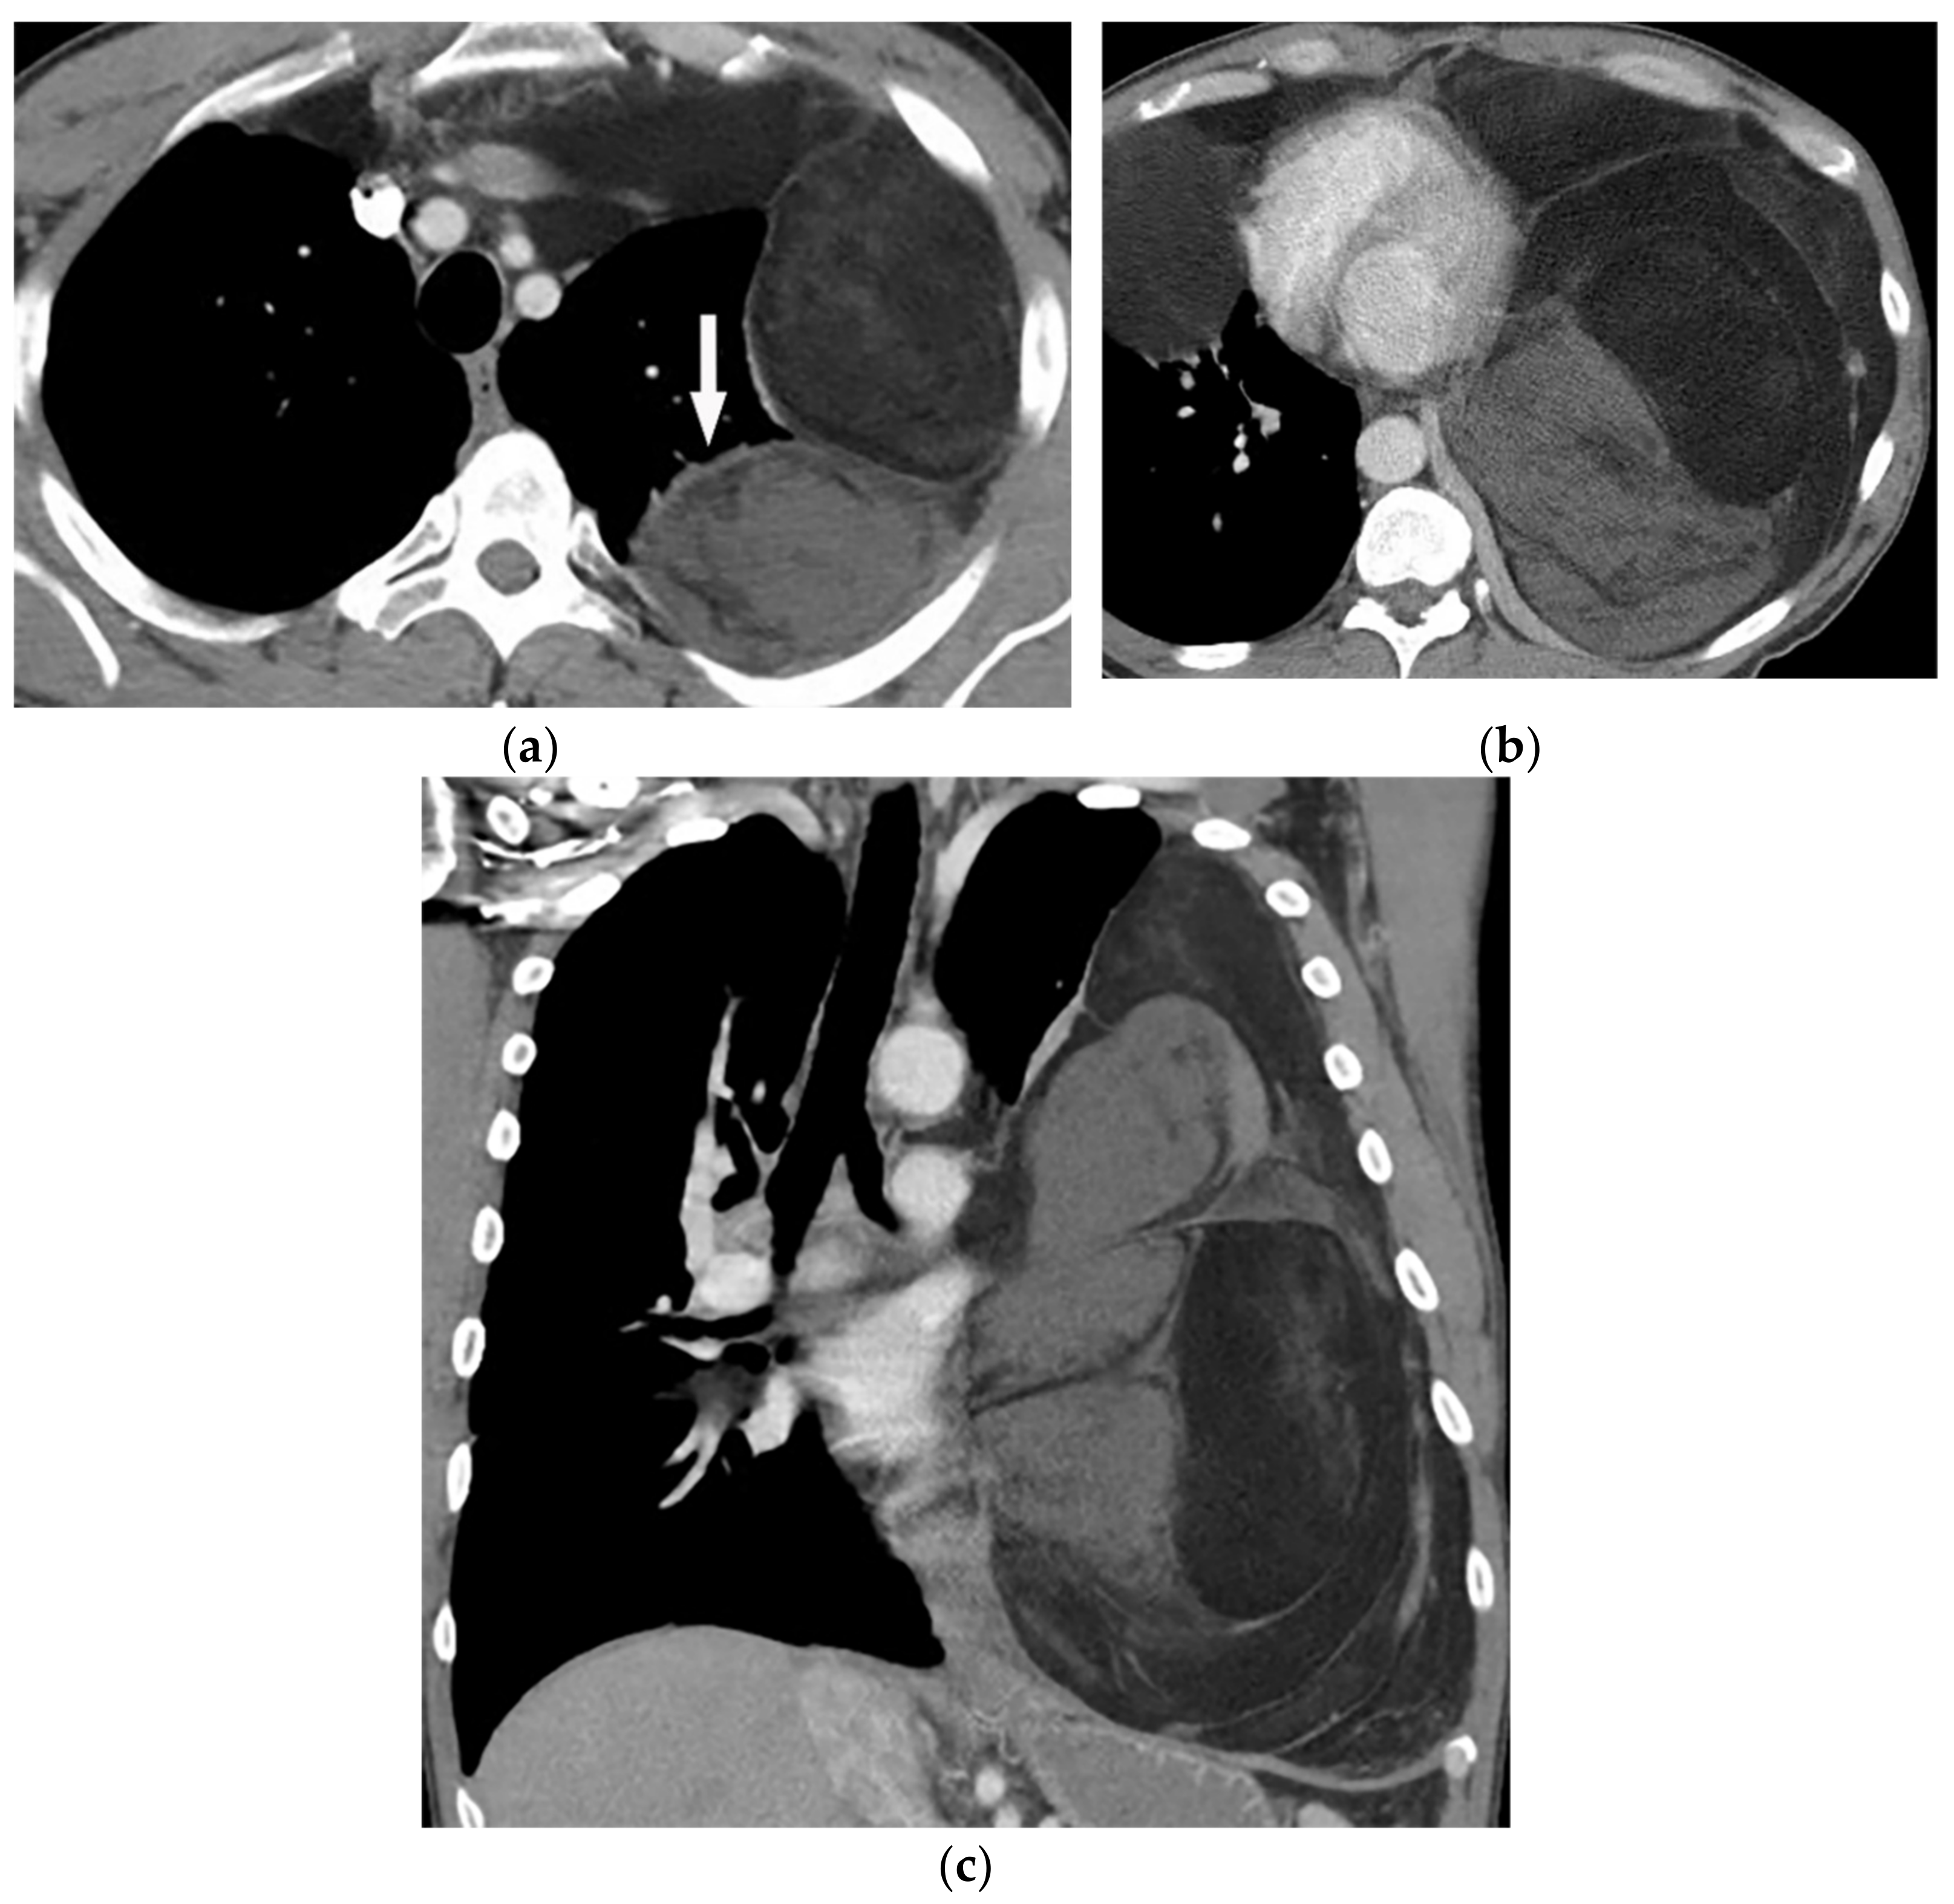

11.3. Mesothelioma

| Mesothelioma | Circumferential pleural thickening, bony or cartilaginous differentiation, unilateral pleural effusion, interlobular septal thickening, tumoral extension, thoracic and extrathoracic metastasis. | T1W: unilateral hyperintense pleural effusion, iso to slightly hyperintense pleural thickening T2W: moderately hyperintense T1WFS + C: typical enhancement is expected |